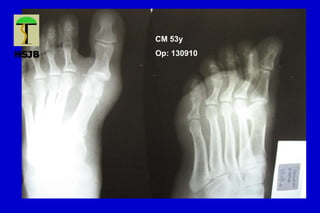

CM 53y

Op: 130910

HALLUX VALGUS

Desviación lateral del hallux, con varo del primer MT

Primer grado o leve Ángulo intermetatarsiano < 15ª

Ángulo MTF < 30ª

Articulación MTF congruente

Sublux sesamoidea mínima

Segundo grado o moderado Ángulo intermetatarsiano entre 15 y 18º

Ángulo MTF entre 20 y 40º

Subluxación MTF

Sesamoideo lateral luxado entre 70 y 100%

Tercer grado o severo Ángulo intermetatarsiano >18-20º

Ángulo MTF > 40º

Hallux pronado

Articulación MTF incongruente

Lx sesamoidea lateral del 100%